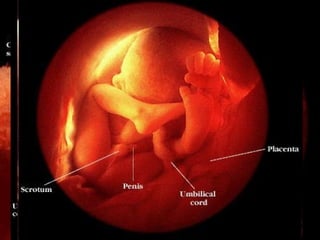

Apariencia de los miembros Día 50 Día 56

Apariencia de losmiembros Día 50 Día 56